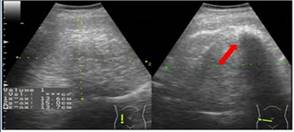

Paciente de 19 años, con embarazo de 19 semanas, quien consultó en febrero del año 2017 al servicio de urgencias de la Clínica Universitaria Colombia, institución de alta complejidad ubicada en Bogotá, que atiende pacientes afiliados al régimen contributivo en el Sistema General de Seguridad Social en Colombia. Consultó por primer episodio de dolor en epigastrio tipo peso, intensidad 4/10, de 10 días de evolución, acompañado de emesis con contenido gástrico; no presentaba antecedentes personales patológicos, farmacológicos ni quirúrgicos; antecedentes ginecológicos, con menarquia a los 15 años, periodos menstruales regulares, primigestante de un embarazo deseado, con asistencia a tres con- troles prenatales. El examen físico arrojó tensión arterial de 110/60 mm/Hg, frecuencia cardiaca de 80 latidos por minuto (l/m), frecuencia respiratoria de 16 respiraciones minuto, escala de Glaslow de 15/15 y temperatura de 36 grados centígrados, con mucosa oral seca, presentaba dolor a la palpación en epigastrio e hipocondrio derecho sin irritación peritoneal, altura uterina de 18 centímetros con feto único longitudinal y fetocardia de 148 l/m, exploración ginecológica sin pérdidas vaginales por lo cual no se realizó examen ginecológico. Con diagnóstico de dolor abdominal en estudio, deshidratación y sospecha de colelitiasis se hospitalizó para inicio de cristaloides parenterales y toma de estudios complementarios. El laboratorio mostró hemograma sin leucocitosis, con un diferencial leucocitario normal; las funciones hepática y renal normales, parcial de orina normal. Se realizó ecografía obstétrica con una biometría para 19 semanas, peso fetal estimado de 264 g, percentil 52 %, placenta normo-inserta, índice de líquido amniótico de 13,5 cm. Para excluir colelitiasis se tomó ultrasonido abdominal que descartó patología biliar y evidenció un tumor sólido de contornos regulares, retroperitoneal derecho, de 15 x 13 x 13 cm, con ecogenicidad heterogénea por probable componente graso, y material ecogénico que proyecta sombra acústica por probable componente óseo (figura1); el estudio se complementó con resonancia magnética, la cual mostró un tumor retroperitoneal de 20 x 13 x 15 cm, encapsulado, con bordes definidos, áreas hiperintensas en secuencia T1, hipointensas en secuencias FatSat por contenido graso; y otras áreas hipointensas en T1 e hiperintensas en T2 por componente quístico tumoral; en el interior del componente graso se hallaron múltiples áreas marcadamente hipointensas que corresponden a tejido de tipo cálcico. Respecto a la glándula suprarrenal derecha, se encontró que ejercía efecto compresivo, desplazando asas intestinales y riñón sin invasión de dichas estructuras. Como posibles diagnósticos se consideraron: teratoma maligno frente a liposarcoma (figura 2). Ante el diagnóstico de tumor retroperitoneal de naturaleza desconocida se solicitó marcador tumoral antígeno del cáncer 125 (CA-125) de 15,7 U/mL, con valor de referencia normal menor a 35 U/mL. Se realizó por parte de radiología intervencionista una biopsia percutánea guiada por ecografía con aguja Tru-cut, se obtuvieron dos cilindros de muestra del componente sólido del tumor, sin complicaciones. En el segundo día de hospitalización la paciente presentó mejoría con resolución del dolor abdominal al manejo con metamizol parenteral, y con tolerancia de la vía oral se dio salida hospitalaria.